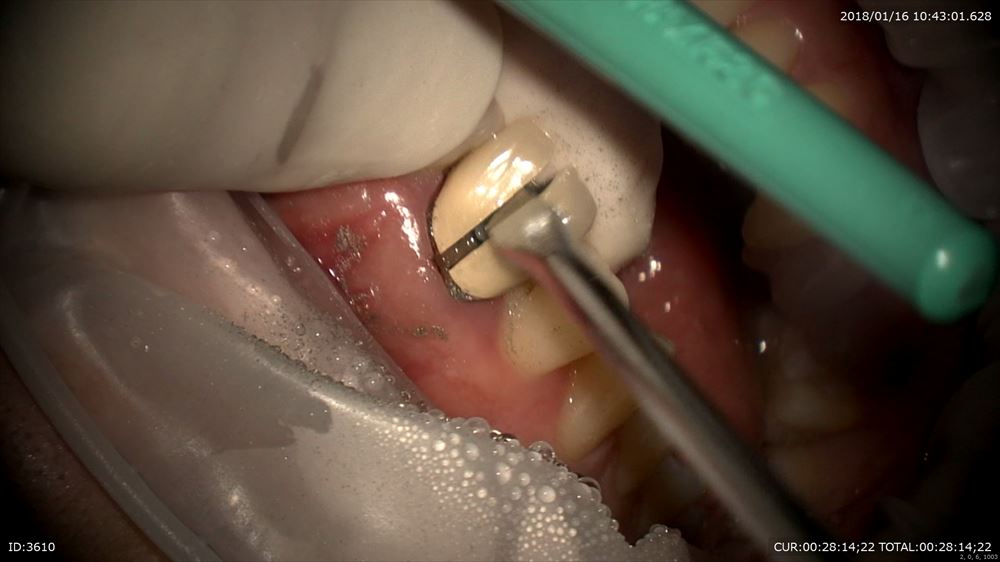

やっぱり銀歯虫歯。ここから最近感染がおきて根管が感染したと思われます。感染を染めて

丁寧に上部形成

中はこんなに汚れています。